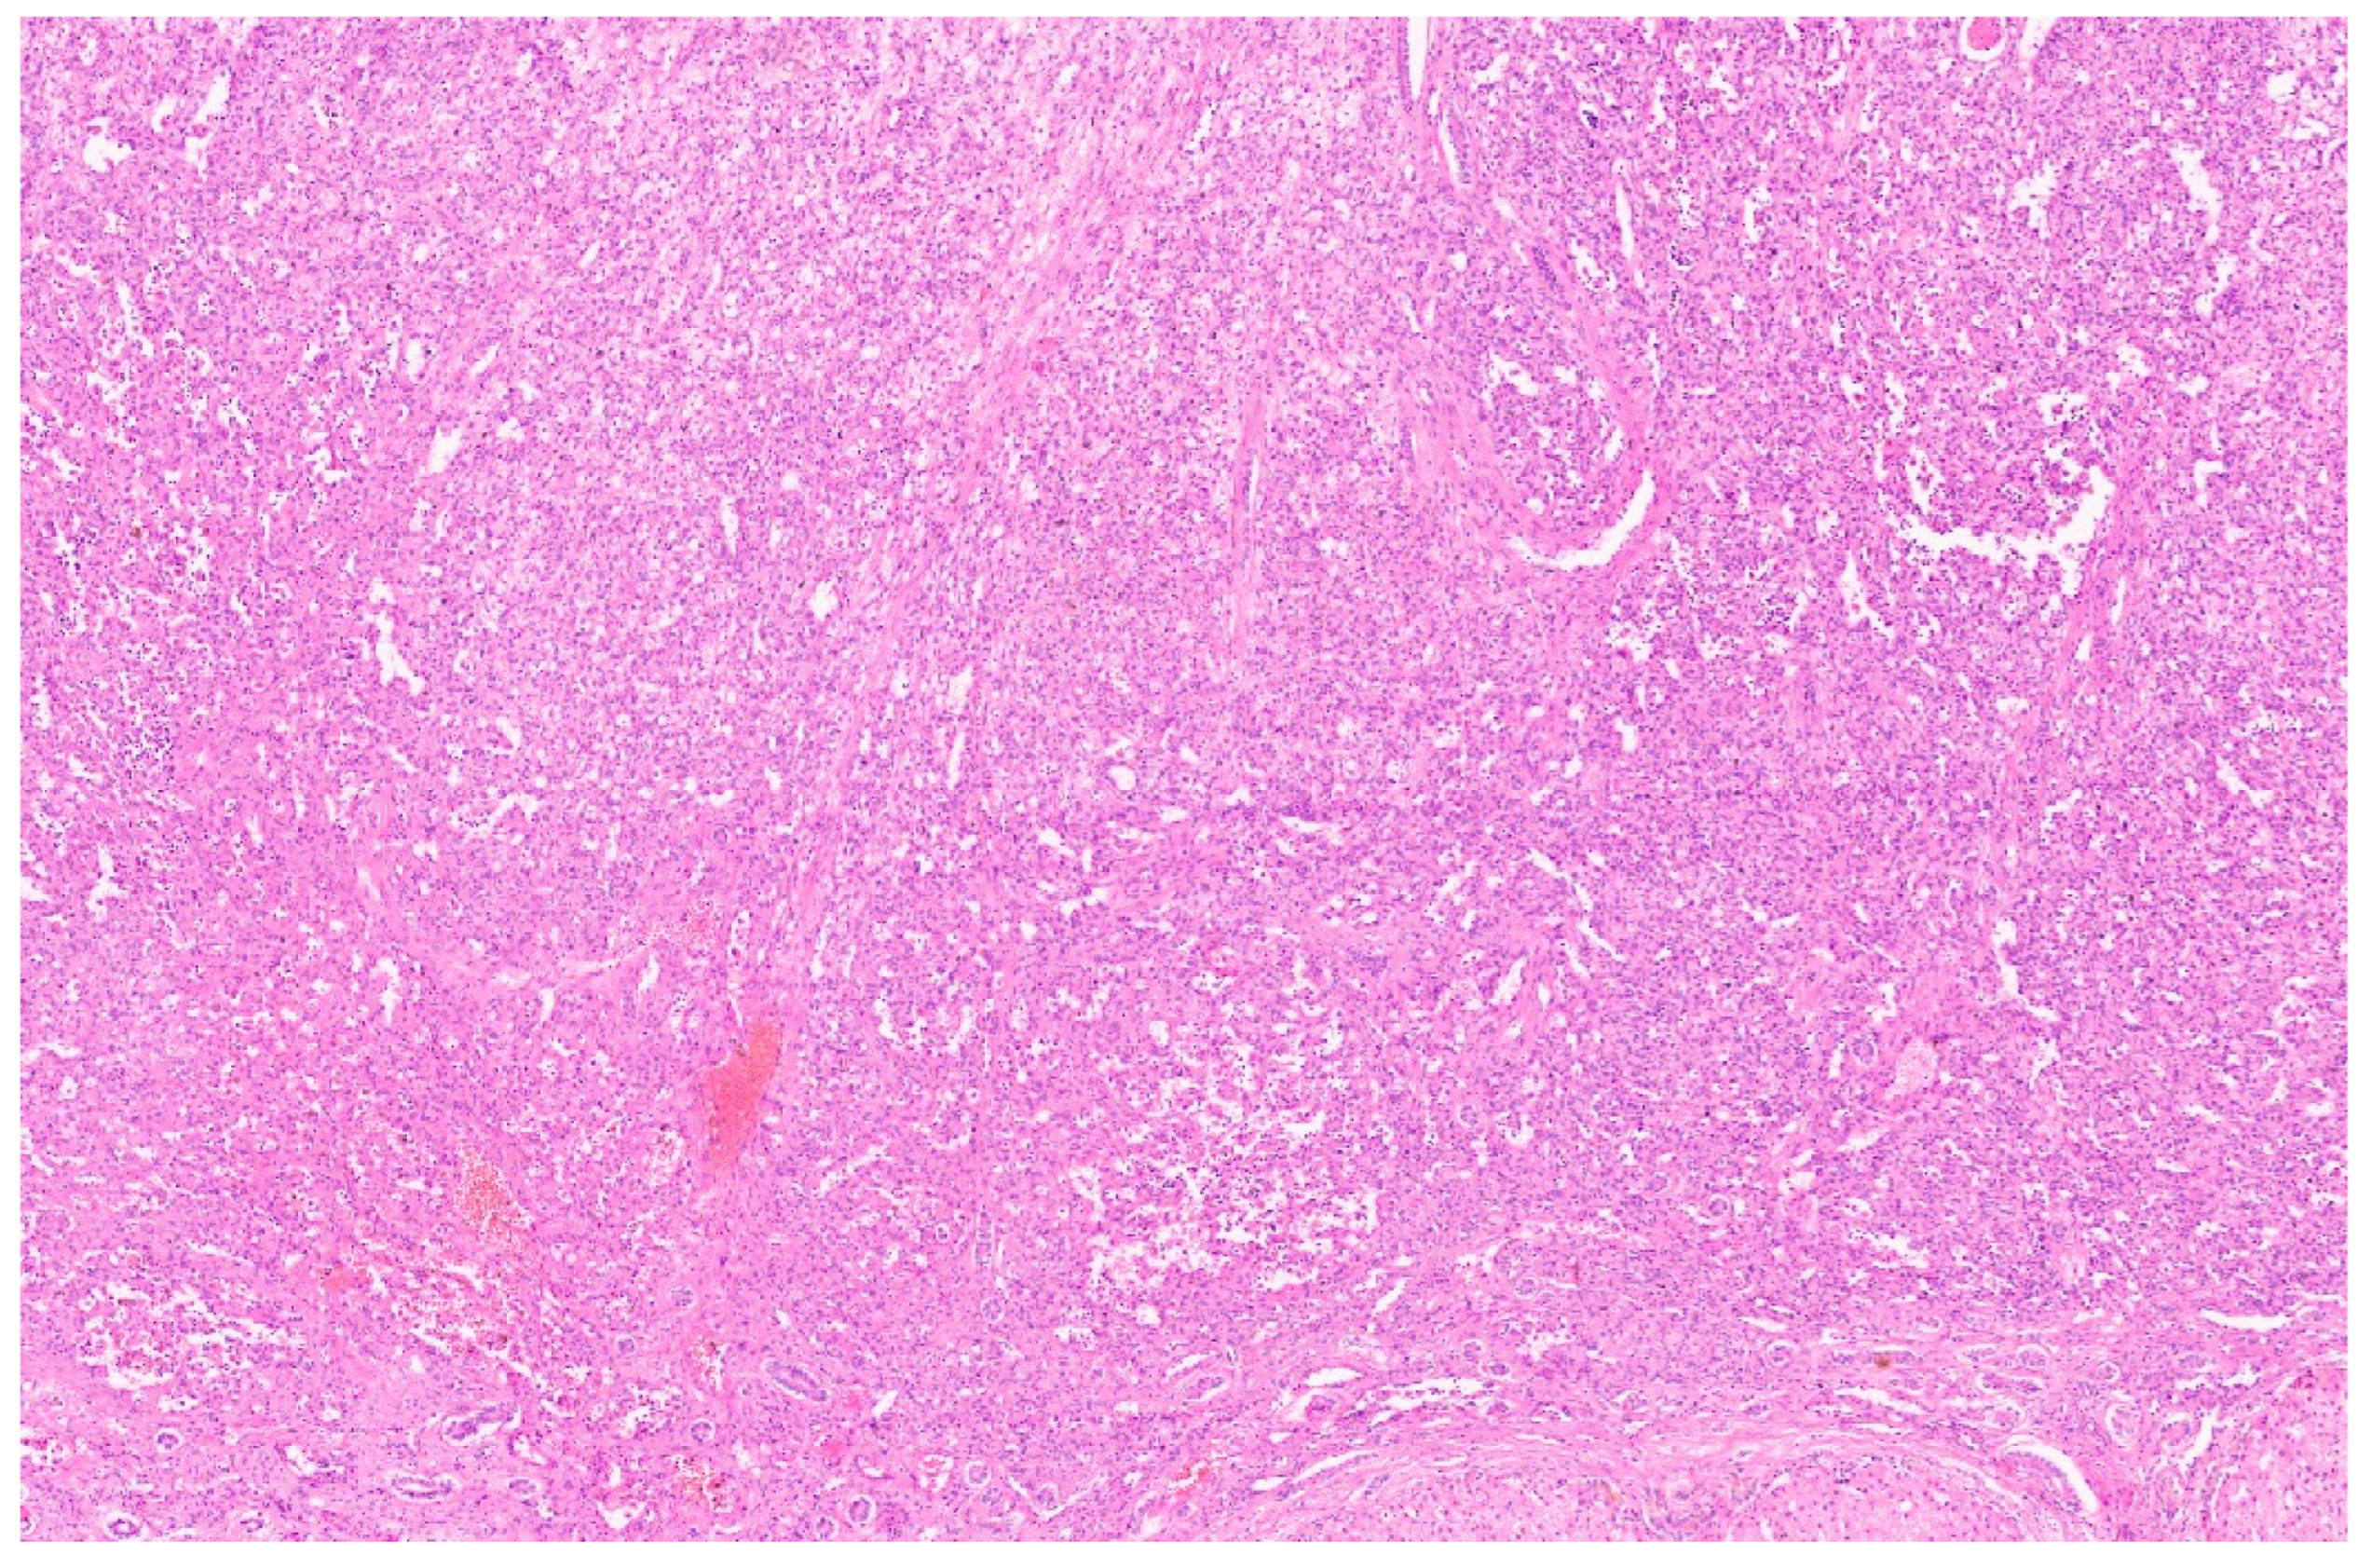

8. Pathology

10.3. Pathology